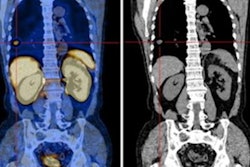

The group culled data from 125 consecutive patients diagnosed with prostate cancer or benign prostate disease (BPD) who underwent Ga-68 PSMA-11 PET/CT scans (uMI 780, United Imaging) at Nanjing First Hospital between February 2019 and May 2021. Patients had received no antitumor treatment before the PET/CT exams.

The researchers extracted 944 prostate cancer features from the images, including shape features, first-order intensity statistics features, and texture features. Then, they narrowed the field to nine features with the least redundancy and greatest correlation with the target tumor, which they used to train the model.

In a subsequent test set (25 patients with prostate cancer and 13 with BPD), the model achieved good predictive performance, with a sensitivity of 0.84, a specificity of 0.77, and a positive predictive value (PPV) and negative predictive value (NPV) of 0.88 and 0.71, according to the findings.

The area under the curve (AUC) value for the model for differentiating prostate histopathology was 0.85, compared with an AUC of 0.63 for visual assessments by trained nuclear medicine physicians who also analyzed the test set. In addition, the radiomics model achieved greater sensitivity, specificity, PPV, and NPV than those of the readers, the researchers wrote.